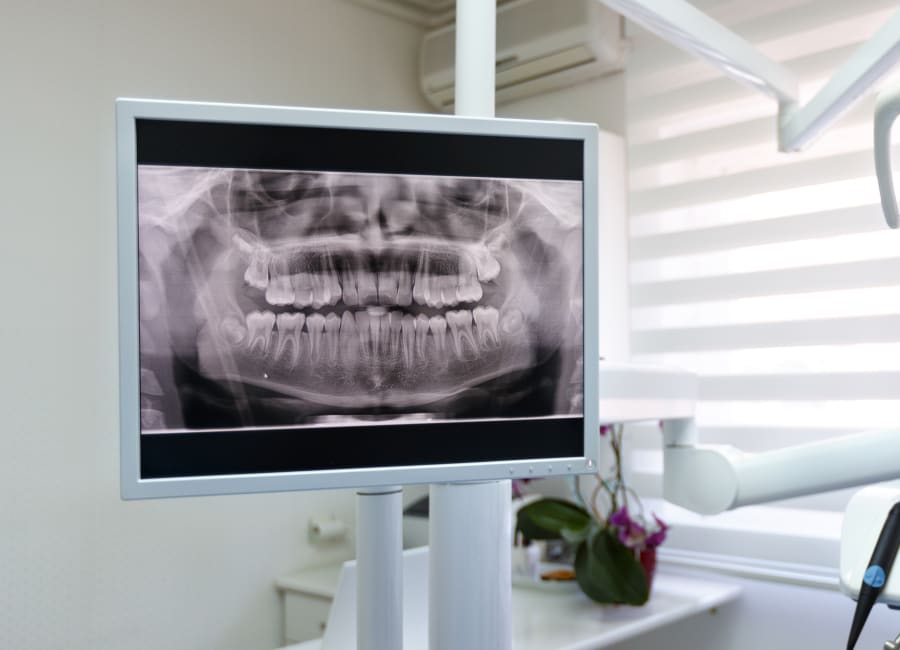

Panoramic X-rays

Panoramic X-ray technology allows your orthodontist to capture a single, comprehensive image of the teeth, jaws, and surrounding oral structures. This wide-view image helps provide an overall understanding of how the teeth and jaws are positioned and developing in relation to each other.

Panoramic X-rays are commonly used to assess tooth development, eruption patterns, root structure, and how the teeth are positioned within the jaws. This information helps us to make careful, informed decisions in the treatment planning phase.